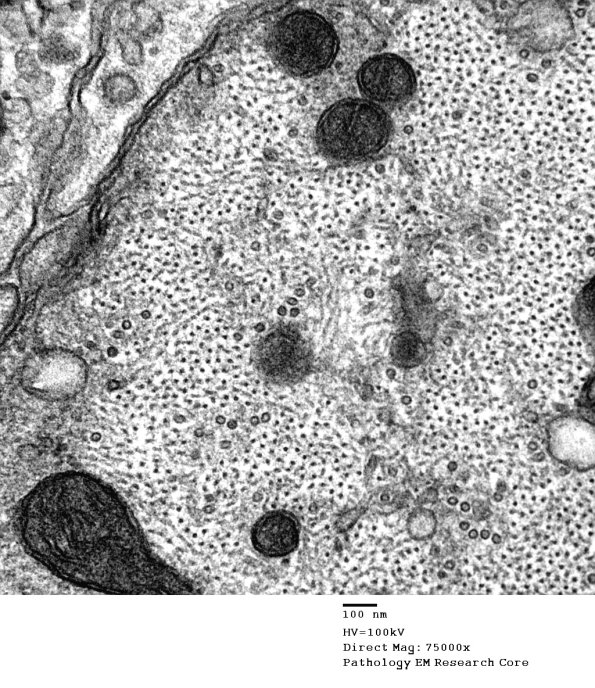

Higher magnification of image #4B9. (electron micrograph)

Washington University Experience | PERIPHERAL NEUROPATHY | 6 AXONAL DEMYELINATION (BASIC PROCESS) | 4B10 Demyelination wo remyelination (Case 4) EM 056 - Copy